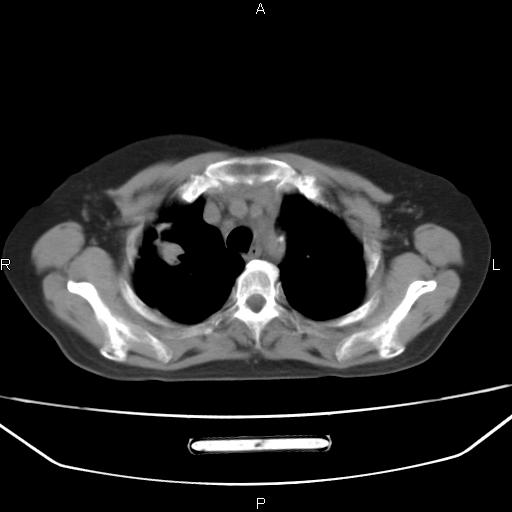

患者,女,66岁。健康体检胸部透视发现右上肺片状阴影。既往无不适,患者自诉三个月前曾有低热病史体温37.5左右一周。用药后缓解。至今无其它不适。请老师们指导指导。

考虑:右肺上叶周围型肺癌(分叶状肿块+砂粒状钙化+胸膜尾征)。

病灶见明显分叶、大小较大(大于3cm?),老年人,多考虑:肺癌,建议穿刺活检。

结合病史不除外感染性病灶。

周围性肺癌可能性大,建议增强

右肺上叶周围型肺癌可能性大。

考虑:右肺上叶周围型肺癌